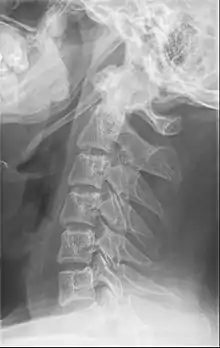

التخيل مهم ويساعد في التشخيص، لذلك يتم تصوير البروز الإبري عن طريق الأشعة المقطعية مع إعادة البناء ثلاثية الأبعاد لأنها التقنية المُثلى في هذا المجال.[2]

البروز الإبري المتضخم يُمكن أن يُري عن طريق صورة بالأشعة السينية لنسيج رخو من الرقبة.